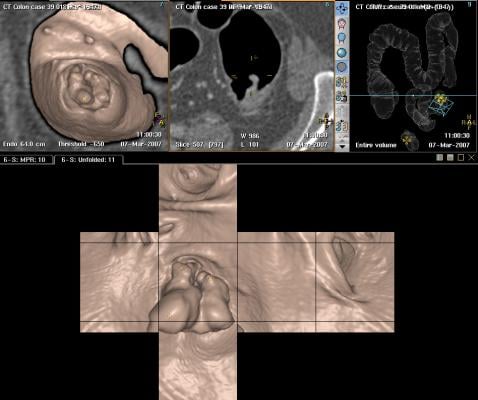

Of the cancers affecting both men and women, colorectal cancer (cancer of the colon or rectum) is the second-leading cancer killer in the U.S., according to the CDC. Screening can find precancerous polyps — abnormal growths in the colon or rectum — so they can be removed before turning into cancer. Screening also helps find colorectal cancer at an early stage, when it is easier to treat.